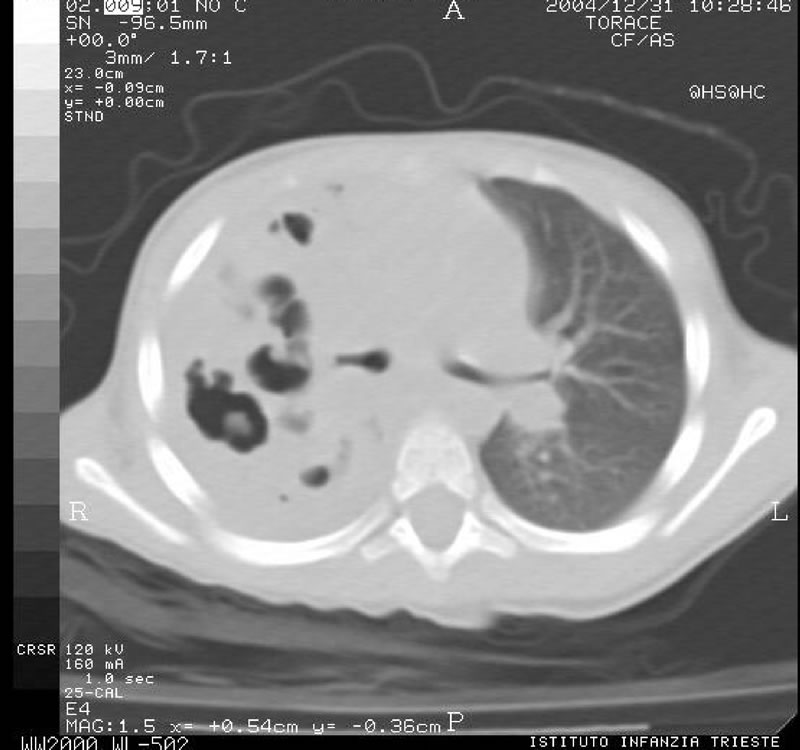

TAC torace eseguita prima e dopo la somministrazione di mezzo dio contrasto per via endovenosa. In corrispondenza del lobo superiore e dei segmenti apicali e del lobo inferiore a destra si apprezza un esteso addensamento polmonare disomogeneo per la presenza di multiple aree ipodense, necrotiche nel cui contesto si apprezzano numerose cavità a contenuto aereo in un quadro compatibile con pneumatocele. Nei settori anteriori e periilari dell'addensamento è apprezzabile broncogramma aereo. Figura 5

Al 18° giorno viene dimessa in terapia con ciprofloxacina somministrato per os. Un controllo a distanza ha evidenziato una completa normalizzazione del quadro radiologico.